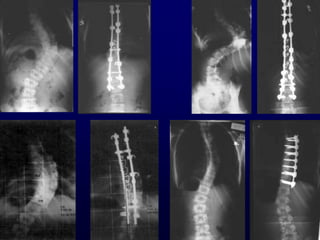

Ζδημπαζήξ Γθεβηθή ΢θμιίςζε

Κυπτώματα - Ταξινόμιση

• Thoracic

• Lumbar

• Thoracolumbar

• Double lumbar and thoracic

• Double thoracic

Thoracic

• Ηύνηςμα T2 - T11 Ημνοθή (ΔΓ)

• ΢οκήζςξ εθζεζεμαζμέκε ζηνμθή.

• Πνμβμιή ηςκ πιεονώκ ζηε θονηή

πιεονά ημο θονηώμαημξ θαη θαζίδεζε

ζηε θμίιε.

• Ακύρςζε ημο εκόξ ώμμο.

• Δύζμμνθε παναμόνθςζε

Ζδημπαζήξ ΢θμιίςζε

Lumbar

• Ηύνηςμα L2 - L4 Ημνοθή (ΑΡ)

• Αζομμεηνία ηεξ μέζεξ με πνμβμιή

ημο ακηίζεημο ηζπίμο.

• Οη γμκείξ ζοπκά ζεςνμύκ όηη ημ

ζθέιμξ ζηε πιεονά ημο θονηώμαημξ

είκαη βναπύηενμ

Thoracolumbar

• Ηύνηςμα T12 - L1

• Πνμθαιεί εθζεζεμαζμέκε

ακηζμννμπία θμνμμύ.

• Ιή απμδεθηή θμζμεηηθά

παναμόνθςζε.

Double Lumbar-Thoracic

• ΢ομμεηνηθά θονηώμαηα.

• ΢οκήζςξ απμδεθηή θμζμεηηθά.

(Ηονηώμαηα ηδίμο μεγέζμοξ)

• Ζθακμπμηεηηθή ηζμννμπία θμνμμύ.

Double thoracic

• Άκς θύνηςμα T1 - T6, Ημνοθή (ΑΡ)

Ηάης θύνηςμα Σ6 – Σ12 Ημνοθή (ΔΓ)

• Γθζεζεμαζμέκε ζηνμθή ηεξ ΢.΢.

• Αζομμεηνία ακώηενμο ζςναθηθμύ

θιςβμύ

Ζδημπαζήξ Γθεβηθή ΢θμιίςζε Κυπτώματα- Ταξινόμιση • Thoracic • Lumbar • Thoracolumbar • Double lumbar and thoracic • Double thoracic

Thoracic • Ηύνηςμα T2- T11 Ημνοθή (ΔΓ) • ΢οκήζςξ εθζεζεμαζμέκε ζηνμθή. • Πνμβμιή ηςκ πιεονώκ ζηε θονηή πιεονά ημο θονηώμαημξ θαη θαζίδεζε ζηε θμίιε. • Ακύρςζε ημο εκόξ ώμμο. • Δύζμμνθε παναμόνθςζε Ζδημπαζήξ ΢θμιίςζε

Lumbar • Ηύνηςμα L2- L4 Ημνοθή (ΑΡ) • Αζομμεηνία ηεξ μέζεξ με πνμβμιή ημο ακηίζεημο ηζπίμο. • Οη γμκείξ ζοπκά ζεςνμύκ όηη ημ ζθέιμξ ζηε πιεονά ημο θονηώμαημξ είκαη βναπύηενμ Ζδημπαζήξ ΢θμιίςζε

Ζδημπαζήξ ΢θμιίςζε Thoracolumbar • ΗύνηςμαT12 - L1 • Πνμθαιεί εθζεζεμαζμέκε ακηζμννμπία θμνμμύ. • Ιή απμδεθηή θμζμεηηθά παναμόνθςζε.

Double Lumbar-Thoracic • ΢ομμεηνηθάθονηώμαηα. • ΢οκήζςξ απμδεθηή θμζμεηηθά. (Ηονηώμαηα ηδίμο μεγέζμοξ) • Ζθακμπμηεηηθή ηζμννμπία θμνμμύ. Ζδημπαζήξ ΢θμιίςζε

Double thoracic • Άκςθύνηςμα T1 - T6, Ημνοθή (ΑΡ) Ηάης θύνηςμα Σ6 – Σ12 Ημνοθή (ΔΓ) • Γθζεζεμαζμέκε ζηνμθή ηεξ ΢.΢. • Αζομμεηνία ακώηενμο ζςναθηθμύ θιςβμύ . Ζδημπαζήξ ΢θμιίςζε